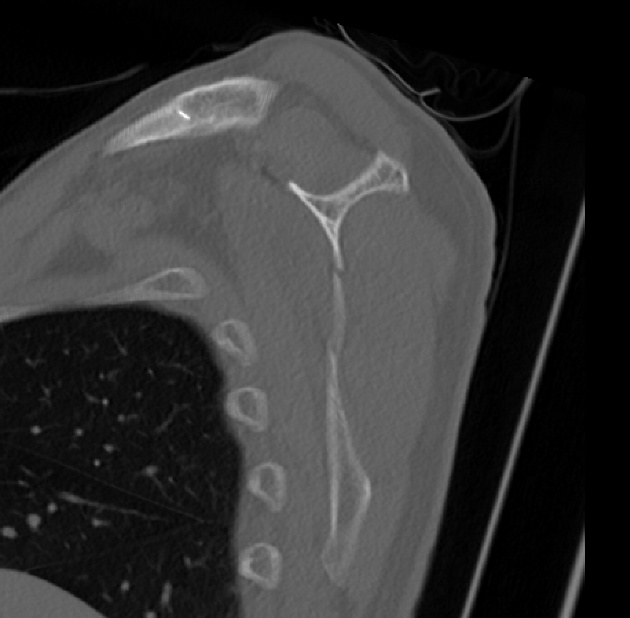

2022.06.07 CT SCAN

- M/50대

- fall down

- X-Ray 검사 상 견갑골 골절의심 됨

- Axial Scan 후 MPR로 Axial, Coronal, Sagittal image Recon 함

- Rib CT 포함하여 검사함.

mildly displaced fracture of body of scapula.